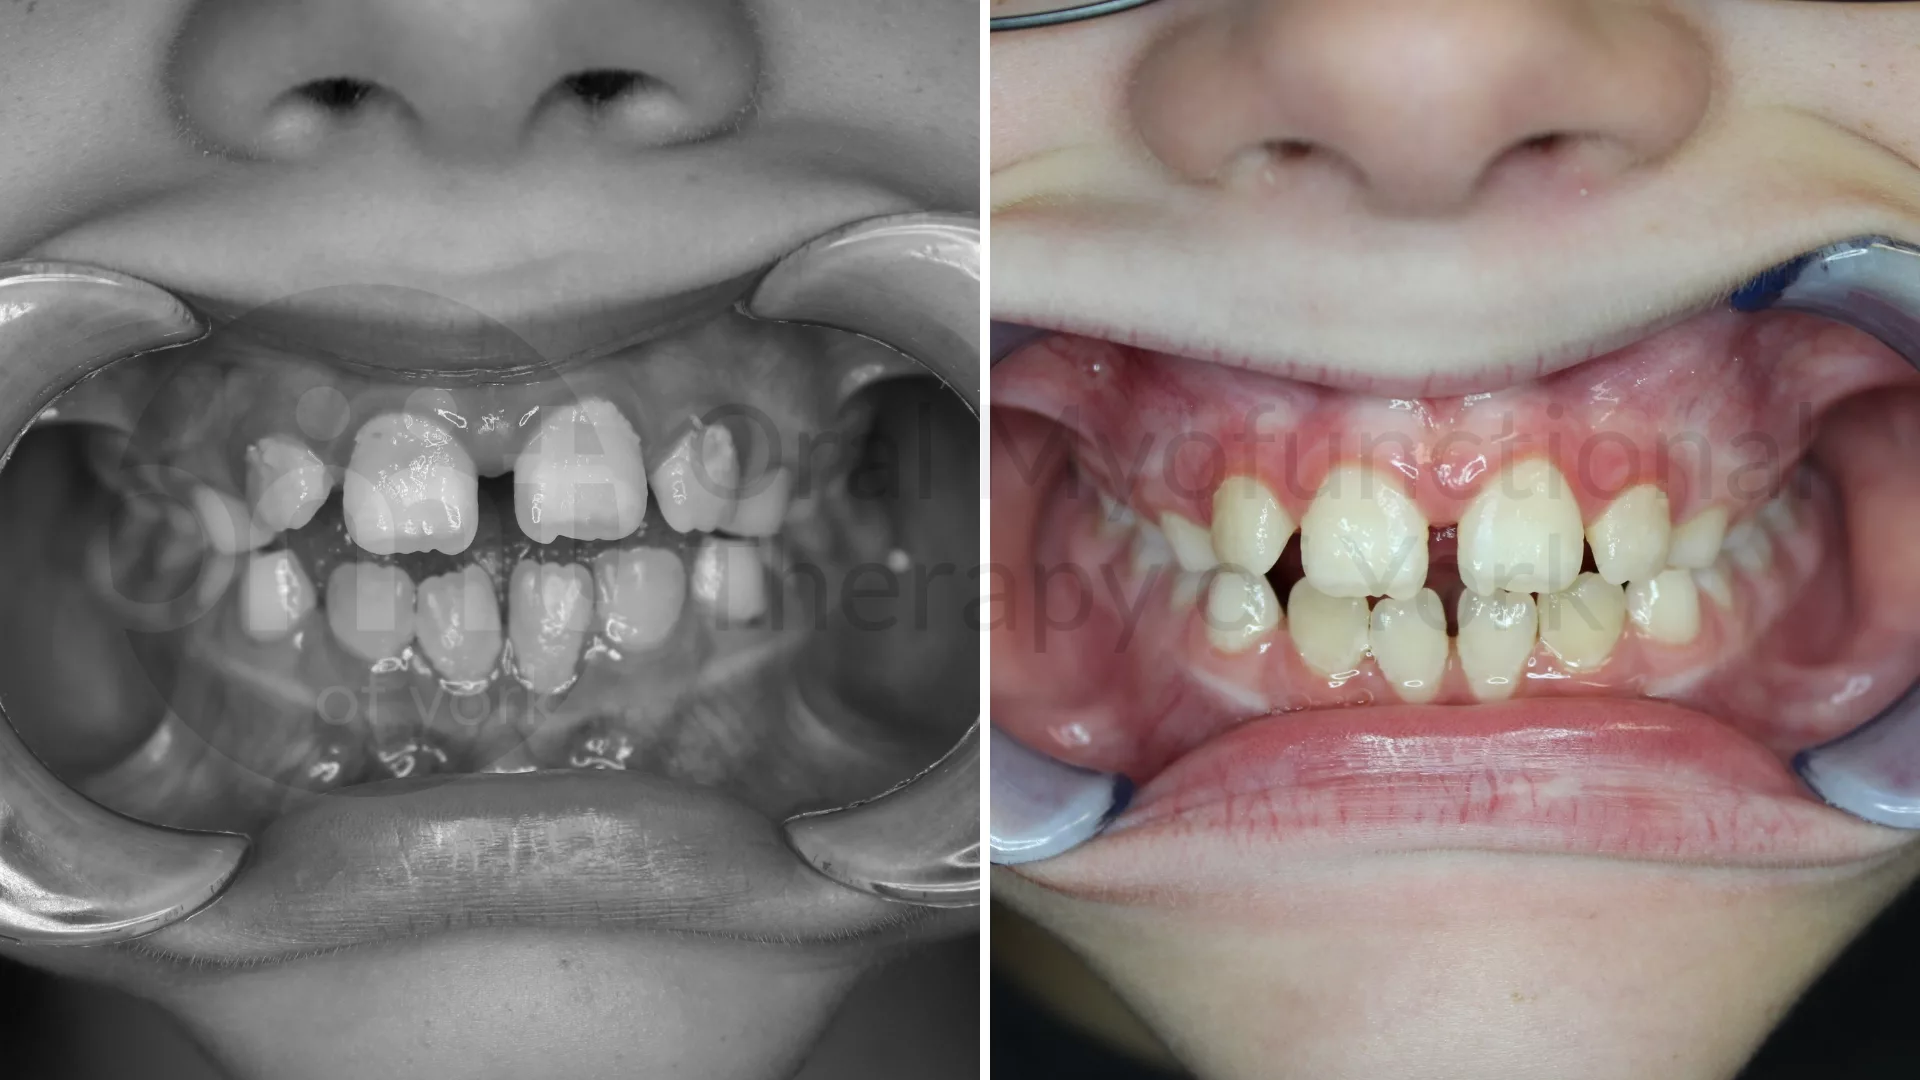

Thumb sucking elimination, therapy and a frenectomy leading to improved growth patterns

Eliminating oral habits such as thumb sucking can lead to better alignment of the teeth and jaws.